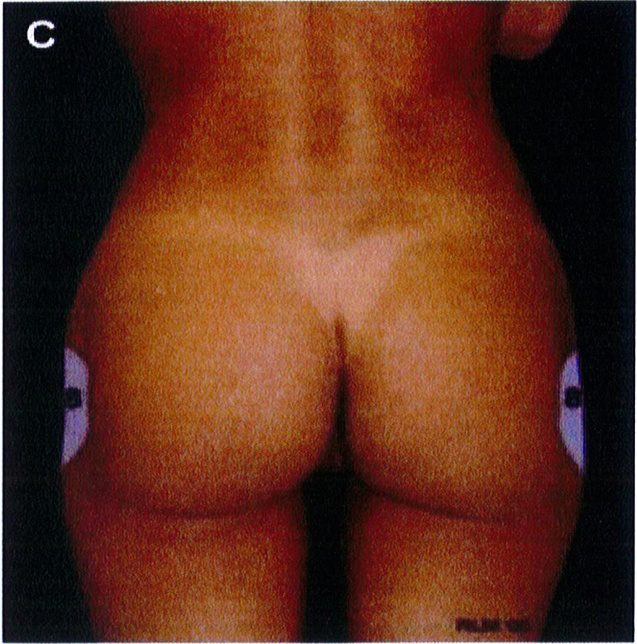

Hình. 2. (A) 10 đơn vị thẩm mỹ vùng sau được mô tả. (B,C) Sau khu vực quan trọng xác định hình dạng khung; bao gồm vùng 1 – 5 và vùng 8. (C) Vùng 8 có thế yêu cầu ghép mô mỡ để tạo đường bờ đẹp (Từ bài báo của Mendieta CG. Gluteal reshaping. Aesthet Surg J 2007;27(6):641-55)

Aesthetic Unit/Zones:Đơn vị thẩm mỹ vùng mông.

1.Sacrum V-zone: Vùng cũng chữ V. 2.Flank: Hông.

7.Diamond zone:inner gluteal/leg injection: Vùng hình thoi: Vùng đùi trong/vùng hút mỡ. 8.Mid-lateral buttock point:Điểm C. 9.Inferior gluteal /posterior leg junc- tion: Mặt sau đùi/mặt dưới mông. 10.Upper back: Lưng.

Aesthetic Unit/Zones:Đơn vị thẩm mỹ vùng mông. 1.Sacrum V-zone: Vùng cũng chữ V. 2.Flank: Hông. 3. Upper buttock : Mông trên, 4. Lower back: Thắt lưng. 5.Outer leg : Bờ ngoài đùi. 6. Gluteus: Mông.

8.Mid-lateral buttock point:Điểm C. 9.Inferior gluteal /posterior leg junc- tion: Mặt sau đùi/mặt dưới mông. 10. Upper back: Lưng.

3.Upper buttock : Mông trên, 4. Lower back: Thắt lưng. 5.Outer leg : Bờ ngoài đùi. 6. Gluteus: Mông.